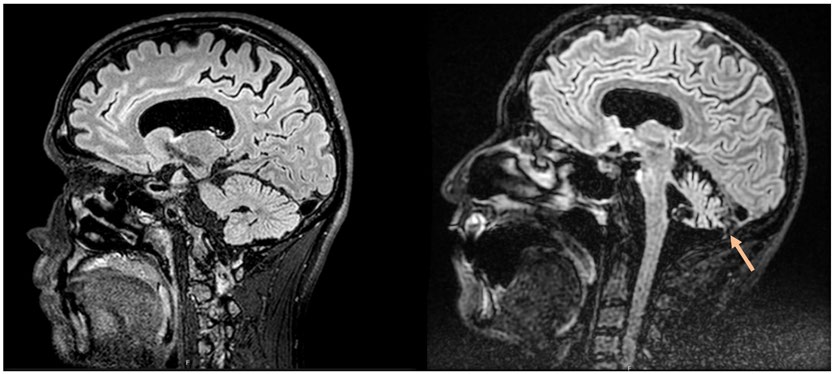

Images in Medicine